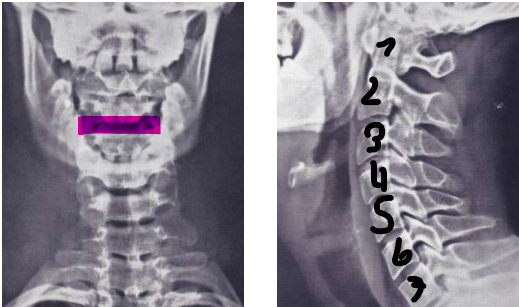

Halswirbelsäule

1. Halswirbelkörper (Atlas)

Halswirbelkörper

Übergang Brustwirbelsäule

Halswirbelkörper (Axis)

Erster und Zweiter Halswirbel

Atlas (1.) & Axis (2.)

Querband Atlas → Dens Axis wird dort gehalten

Bezeichnung von

vorne nach hinten

seitlich

AP - anterior posterior

lateral

Anatomie der Wirbel im Gefüge der Wirbelsäule seitlich